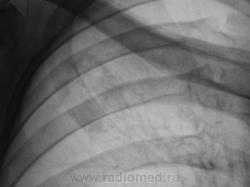

Через год, после проведенного "специфического" лечения.

Рентгенограмма.

Я бы остановилась на множественных туберкулемах s1-2 обоих легких,Туберкулемы не однородны.за счет уплотнения,пл очаги.фиброз.

Слева туберкулома и корень подтянут Справа-очаги отсева .Динамика типичная- лечим.лечим-а туберкуломе хоть бы хны!

Туберкулёма только в С1+2 слева, как дела давно минувших дней.  Произошла реактивация туберкулёзного процесса с развитием двустороннего очагового туберкулёза. Имеется положительная динамика в виду некоторого уплотнения очагов. Таково мое мнение.